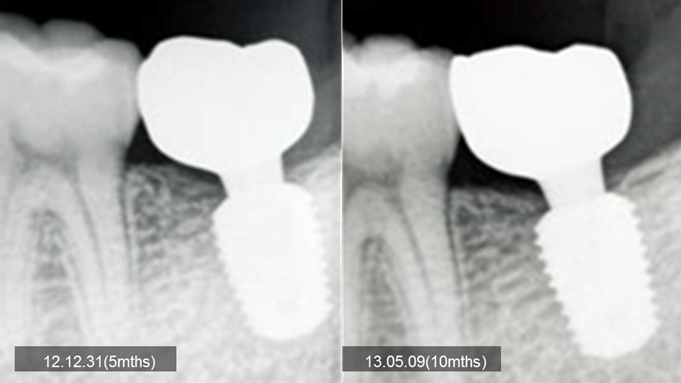

“AnyRidge implant enables fast and stable

osseointegration at this extreme case of bone defect. ”

Clinical case: Bone filling into the bottom of deepest thread at 8.0mm AnyRidge fixture

- Courtesy of Dr. Kwang Bum Park -

Keywords

AnyRidge, Knifethread ,extraction socket, ,initial stability ,Allograft, ,osseointegratio ,Dr. Kwang Bum Park, , Mandibular, Single replacement, AnyRidge, Mega-oss,

Products used

Implant system-AnyRidge, Regeneration-Mega-Oss